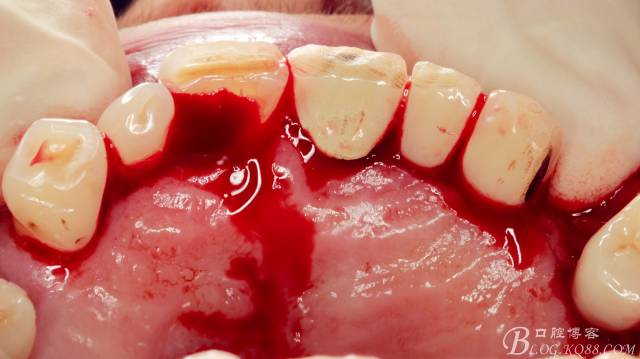

術(shù)中

局麻下做齦溝內(nèi)切口

翻瓣,長柄球鉆清掃薄薄的骨皮質(zhì),暴露出牙冠,動(dòng)作一定要輕柔,感覺就像在雞毛撣子一樣撣花瓶上的灰一樣,因?yàn)楣呛脱烙再|(zhì)有明顯的密度差異,手感上面差別比較明顯。